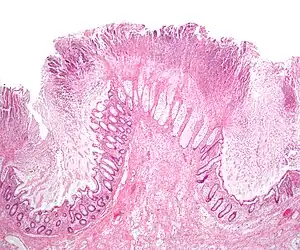

Colectomy (col- + -ectomy) is bowel resection of the large bowel (colon). It consists of the surgical removal of any extent of the colon, usually segmental resection (partial colectomy). In extreme cases where the entire large intestine is removed, it is called total colectomy, and proctocolectomy (procto- + colectomy) denotes that the rectum is included.

Indications

Some of the most common indications for colectomy are:

- Colon cancer

- Diverticulitis and diverticular disease of the large intestine

- Trauma

- Inflammatory bowel disease such as ulcerative colitis or Crohn's disease. Colectomy neither cures nor eliminates Crohn's disease, instead only removing part of the entire diseased large intestine. A colectomy is considered a "cure" for ulcerative colitis because the disease attacks only the large intestine and therefore will not be able to flare up again if the entire large intestine (cecum, ascending colon, transverse colon, descending colon and sigmoid colon) and rectum are removed. However, it does not always take away extra-intestinal symptoms.

- Bowel infarction, which may be a complication of ischemic colitis

- Typhlitis

- Hirschsprung's disease

- Prophylactic colectomy can be indicated in some forms of polyposis, Lynch syndrome and certain cases of inflammatory bowel disease because of high risk for development of colorectal cancer.